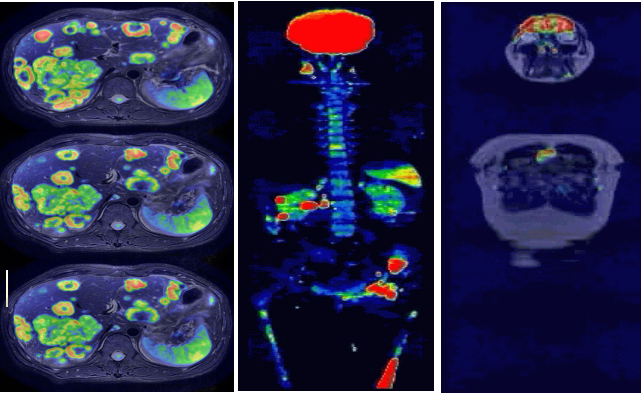

5.全身系统 8分钟类PET成像

全身弥散成像,又称作类PET成像,凭借此项技术,放射科大夫可以借助磁共振系统,无辐射无剂量的筛查病人,对肿瘤患者进行大范围扫描,寻找原发病灶,对肿瘤转移进行分级,对化疗病人进行全身疗效评估,等等。所有这些信息,以前患者只有选择昂贵且有辐射的SPECT或者PET才有可能获得。GE的全身弥散成像,建立在最均匀的磁体,最保真的ECO梯度和最均匀的光纤射频信号之上,是业内唯一能大规模开展临床全身弥散成像的厂家。